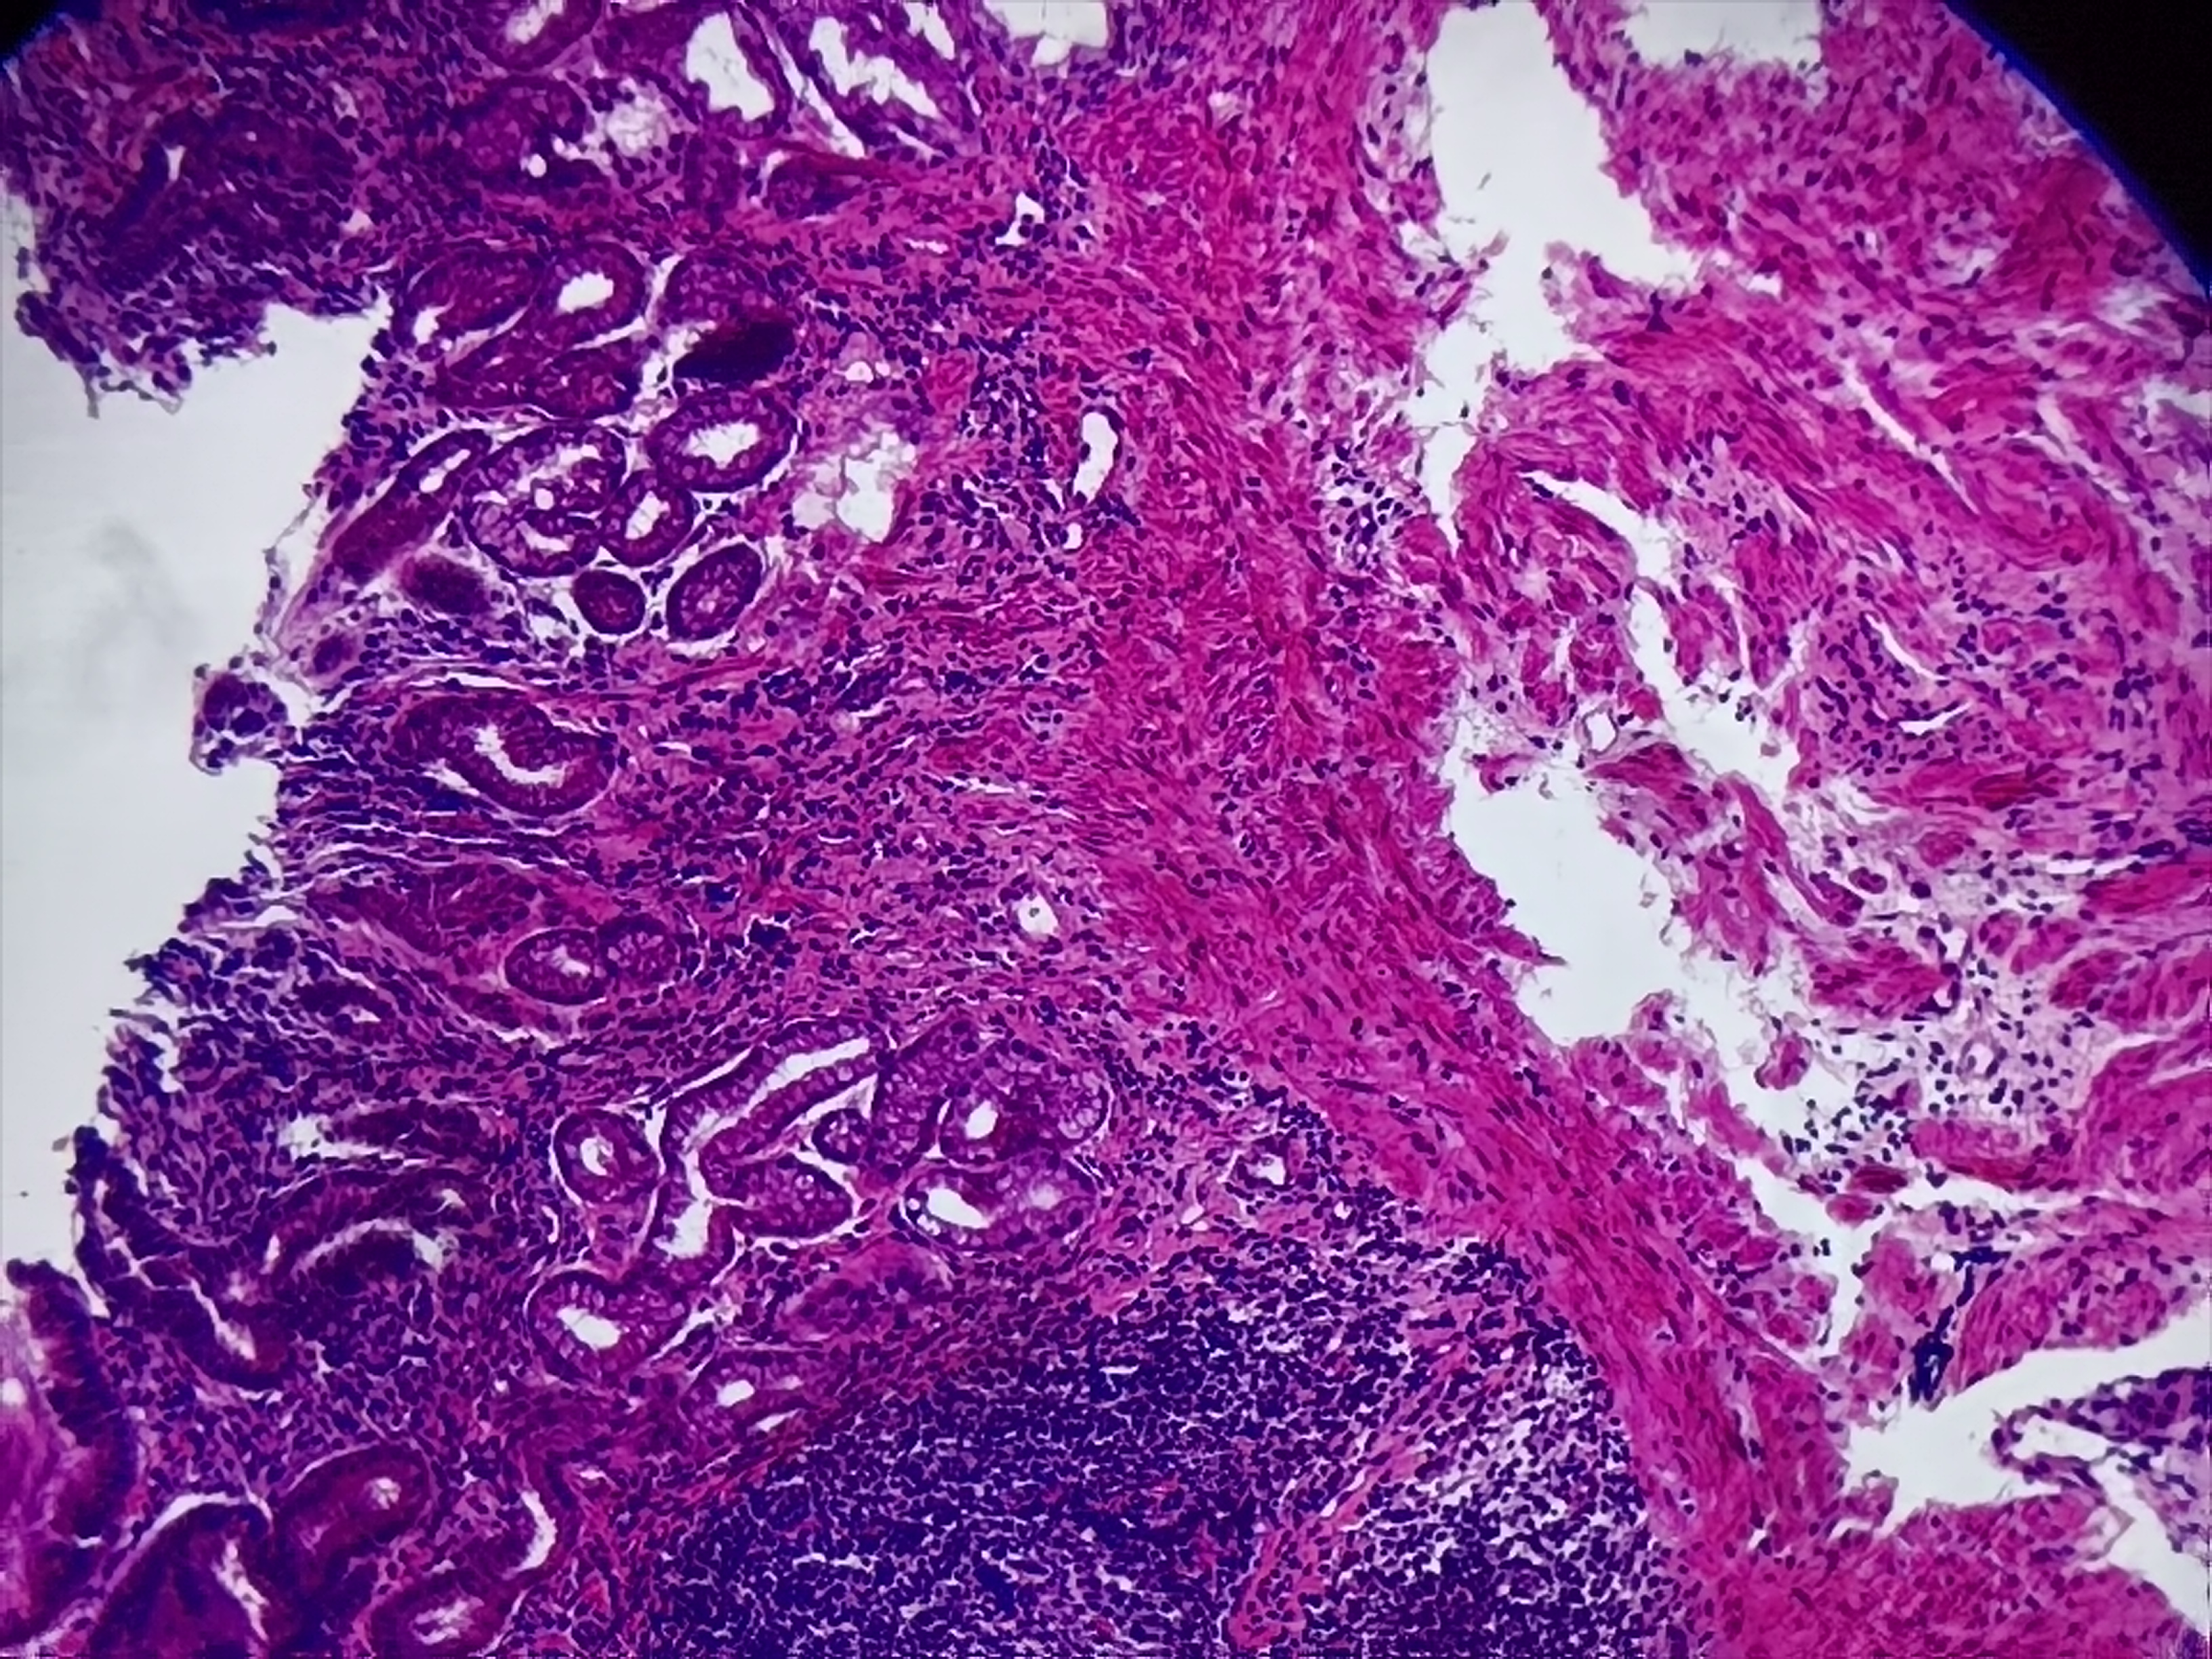

胃窦活检

胃窦部分粘膜表面血痂及少量渗血,多发白苔溃疡

胃窦粘膜活检

灰白色组织1块

良性的,片子质量不好!

考虑慢性活动性炎,图3靠右上方的那一个区域看上去有些模糊, 薄切一张重染再看看。